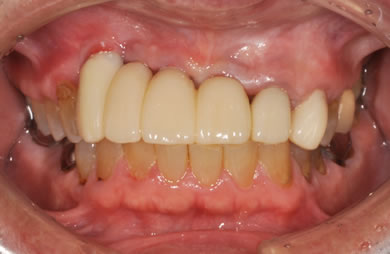

治療後

• 治療後